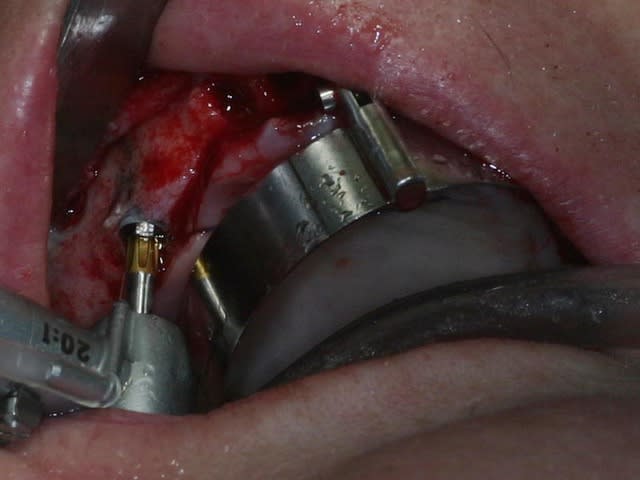

bon, toujours aussi speed je suis, mais après certaines réclamations, et malgrès ma réticence à poser un cas non "consolidé", voici en avant première mon premier all on 4, version photos ratées et non retouchées, mais... speed je suis je vous disais ;)

sto le bla bla, et pasons le diaporama... bon voyage au pays de la mise en charge immédiate totale au maxillaire de fille carole sur dame ginette, une patiente en or que j' adore, et pour qui je suis très très heureuse d' avoir pu réaliser cette chirurgie et la première étape prothétique.....

Tu as utilisé des Nobel Speedy si je ne me trompe pas.

Tu as eu un couple final de 50N au maxillaire ? Si c'est le cas, bravo.

Peux tu nous en dire un peu plus sur les implants, leurs diamétres et leur longueurs ?